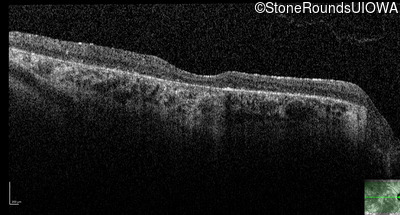

Age at visit: 38 years

This 38 year old woman had normal vision until age 22 when she noticed poor night vision when working as a camp counselor after college. Her hearing loss was first noticed at age 3 and was correctable with hearing aids.

Age at visit: 41 years

Age at visit: 42 years